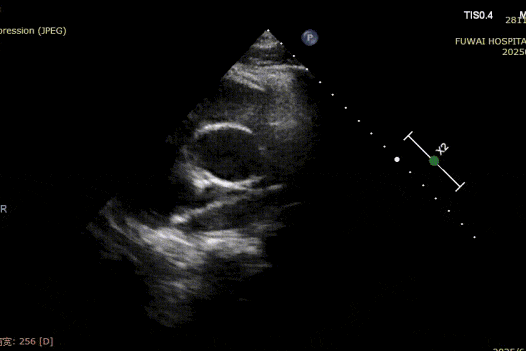

1. O TEA foi central em localização, com diâmetro medido de aproximadamente 8,1mm (visão bicaval) e 8,2mm (visão aórtica de eixo curto).

4. Não havia borda aórtica, e as bordas inferior e posterior eram relativamente moles.

O procedimento foi guiado pela ETT seguindo o procedimento PAN desenvolvido no Hospital Fuwai. Essa técnica de imagem livre de radiação e em tempo real oferece visualização anatômica de alta resolução, garantindo a colocação precisa do dispositivo e minimizando as complicações-particularmente valiosas em pacientes jovens em idade reprodutiva.